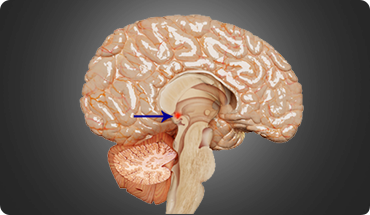

Pituitary tumours are abnormal growths within the pituitary gland, a small gland located near the base of the brain. Pituitary tumours can be either functioning or non-functioning. Functioning tumours secrete pituitary hormones that can lead to a clinical syndrome, while non-functioning tumours are those that can cause a syndrome by not secreting pituitary hormones.